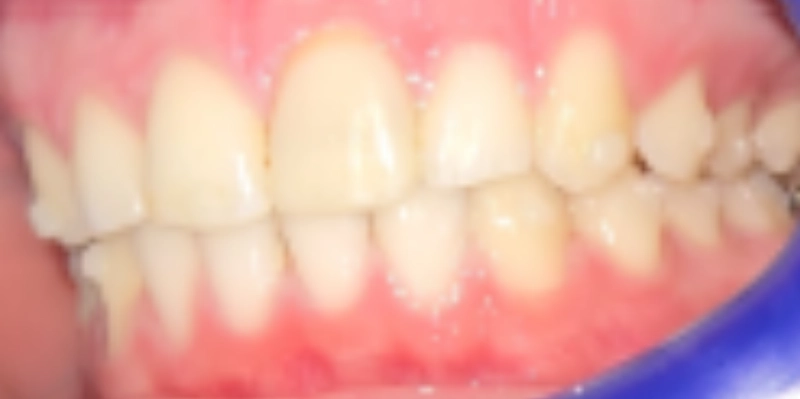

תמונות לפני ואחרי טיפול

אחרי

בסיום הטיפול התקבלה תוצאה אסתטית ותפקודית ברמה גבוהה מאוד. יחסי הסגר שופרו, הצפיפות נפתרה, הקשתות יושרו, והמראה של האזור הקדמי השתנה באופן משמעותי. מעבר ליישור השיניים, הטיפול הצליח להתמודד עם מצב מורכב של שן קדמית לאחר חבלה, תוך שמירה על זהירות ביולוגית גבוהה ותכנון זהיר של כל שלב. זהו מקרה שממחיש כיצד אורתודונטיה מותאמת אישית איננה רק בחירה במכשור מסוים, אלא היכולת לתכנן את סדר הפעולות הנכון, לשלוט בתנועת שיניים באופן סלקטיבי, להתחשב במגבלות הביולוגיות של כל שן, ולהוביל לתוצאה אסתטית מצוינת גם כאשר נקודת הפתיחה מורכבת במיוחד.